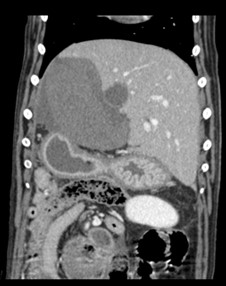

A CT scan revealed Riley was suffering from two liver lobe torsions (LLT), an extremely rare complaint in animals and especially in dogs.

“Riley was stabilised with the help of our anaesthesia team and underwent a CT scan. We the assistance of our imager on duty, we diagnosed Riley with torsion of two of his liver lobes.